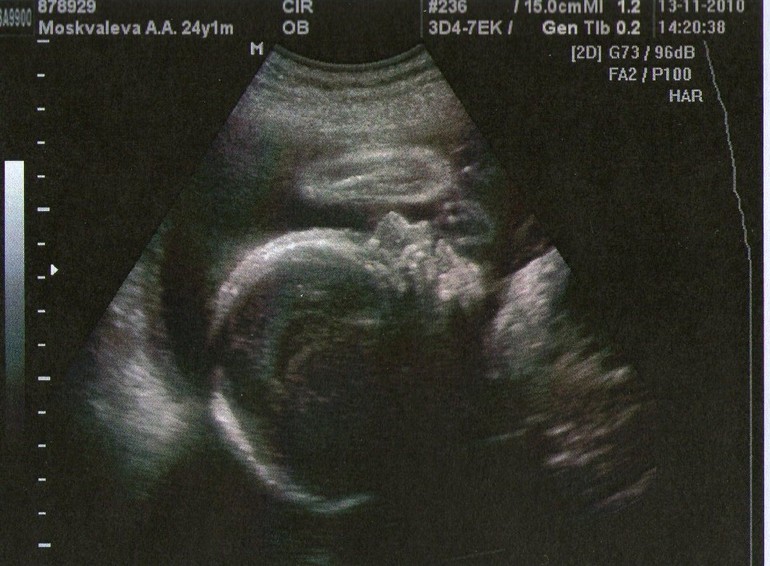

Я очень хотела сына. Прям бредила мальчиком вплоть до 18-й недели, когда меня наконец-то обрадовали, что у нас будет сын.